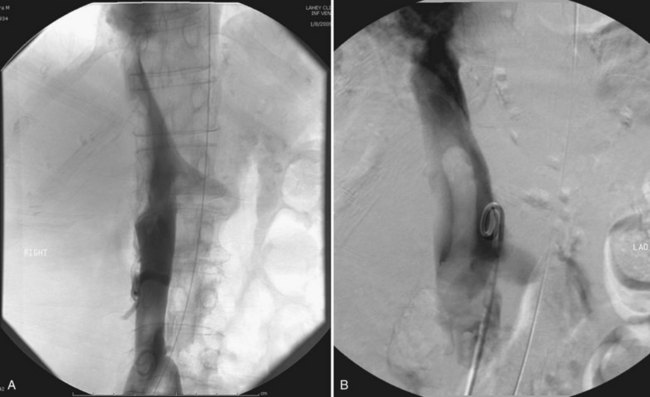

Tumor thrombus involving the IVC should be suspected in patients with lower extremity edema, varicocele, dilated superficial abdominal veins, proteinuria, pulmonary embolism, right atrial mass, or nonfunction of the involved kidney. MR venography is the authors’ preferred study for evaluating the presence and the distal extent of involvement of the IVC (Pritchett et al, 1987; Goldfarb et al, 1990) (Fig. 54–86). The use of invasive inferior vena cavography is limited to those patients with a nondiagnostic MR venogram or ultrasound evaluation, in those in whom MRI is contraindicated, and in patients who underwent preoperative angioinfarction with coils that would produce scatter leading to poor quality MR images (Fig. 54–87). Transesophageal echocardiography (Treiger et al, 1991; Glazer and Novick, 1997) and transabdominal Doppler ultrasonography (McGahan et al, 1993) are also useful. In patients with known IVC tumor thrombus the authors perform intraoperative transesophageal echocardiography to evaluate the distal extent of the tumor thrombus before making the incision.

Figure 54–86 A, Coronal MR image demonstrates tumor extending to the level of the diaphragm. B, Sagittal MR reconstruction demonstrates thrombus that extends farther into the right atrium. The patient would eventually require cardiopulmonary bypass and deep hypothermic circulatory arrest.

Figure 54–87 A and B, Preoperative cavogram demonstrating filling defect at the T10 level consistent with tumor thrombus in a patient with a large right renal mass. The patient required cardiopulmonary bypass and deep hypothermic circulatory arrest.